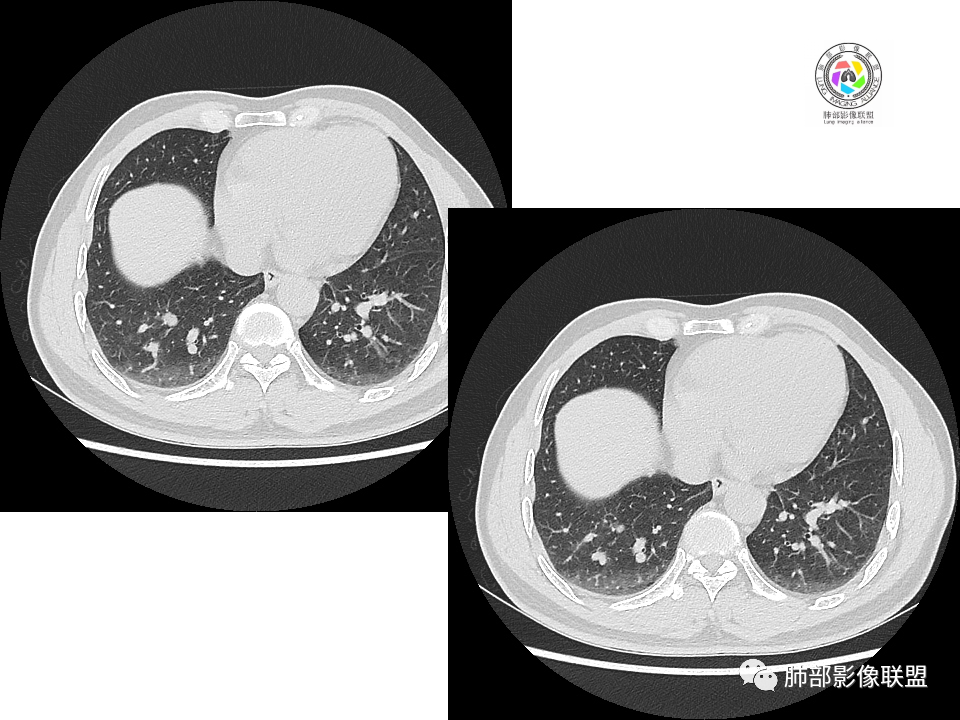

2.右肺下叶背段胸膜下块影,边界清楚光整,上下极见磨玻璃晕,未见明显分叶毛刺和棘状突起,未见胸膜凹陷或胸壁侵入。密度均匀,轻度不均匀强化。未见支气管进入。

3.右肺中叶外侧段胸膜下散在小片影,磨玻璃密度为主,边界不清,支气管相关。符合炎性特征!

4.右肺下叶基底段支气管血管束旁小结节影,边界清楚,强化不明显。注意,这结节在“遥远的”基底段。

显然本例焦点在于背段那个边缘光整的块影!

1.边缘光整干净,大病灶缺乏坏死等,不符合鳞癌影像学特征。尽管有吸烟史,还是偏年轻。

2.边缘光整,会是小细胞癌或是大细胞癌吗?小细胞癌的肺门纵隔淋巴结增大往往十分夸张,该患者不符合。

注意,基底段支气管血管束旁的小结节影,即便是淋巴结,也与背段病灶引流途径不符。

3.会是转移瘤吗?如前所述,患者偏年轻,缺乏相关原发肿瘤病史,强化程度不高,似乎也缺乏支持点。

4.良性占位绕不过去,如发生于该部位的孤立性纤维瘤等……

病灶不均匀强化可以将含液支气管囊肿排除在外。

5.慢性感染灶。缺乏临床表现,强化不显著会想到继发性肺结核,背段病灶过于光整均匀,周边过于干净使人狐疑,且“成掎角之势”的中叶病灶结核灶特点也着实不多。

有老师分析,多发病灶有磨玻璃晕,可以符合隐球菌感染,确实如此。但背段边缘如此锐利的块影还是更容易让人联想到新生物。